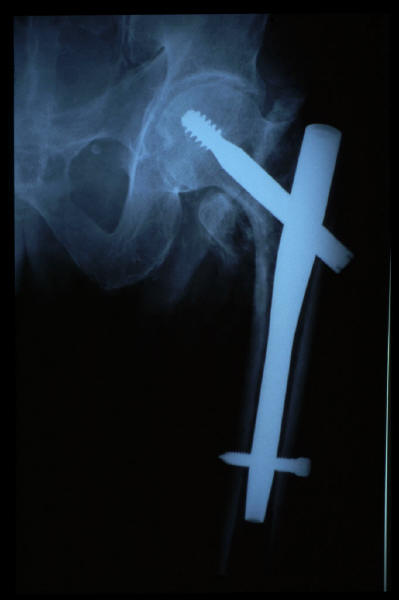

Fractura intertrocantérea de fémur, osteosíntesis